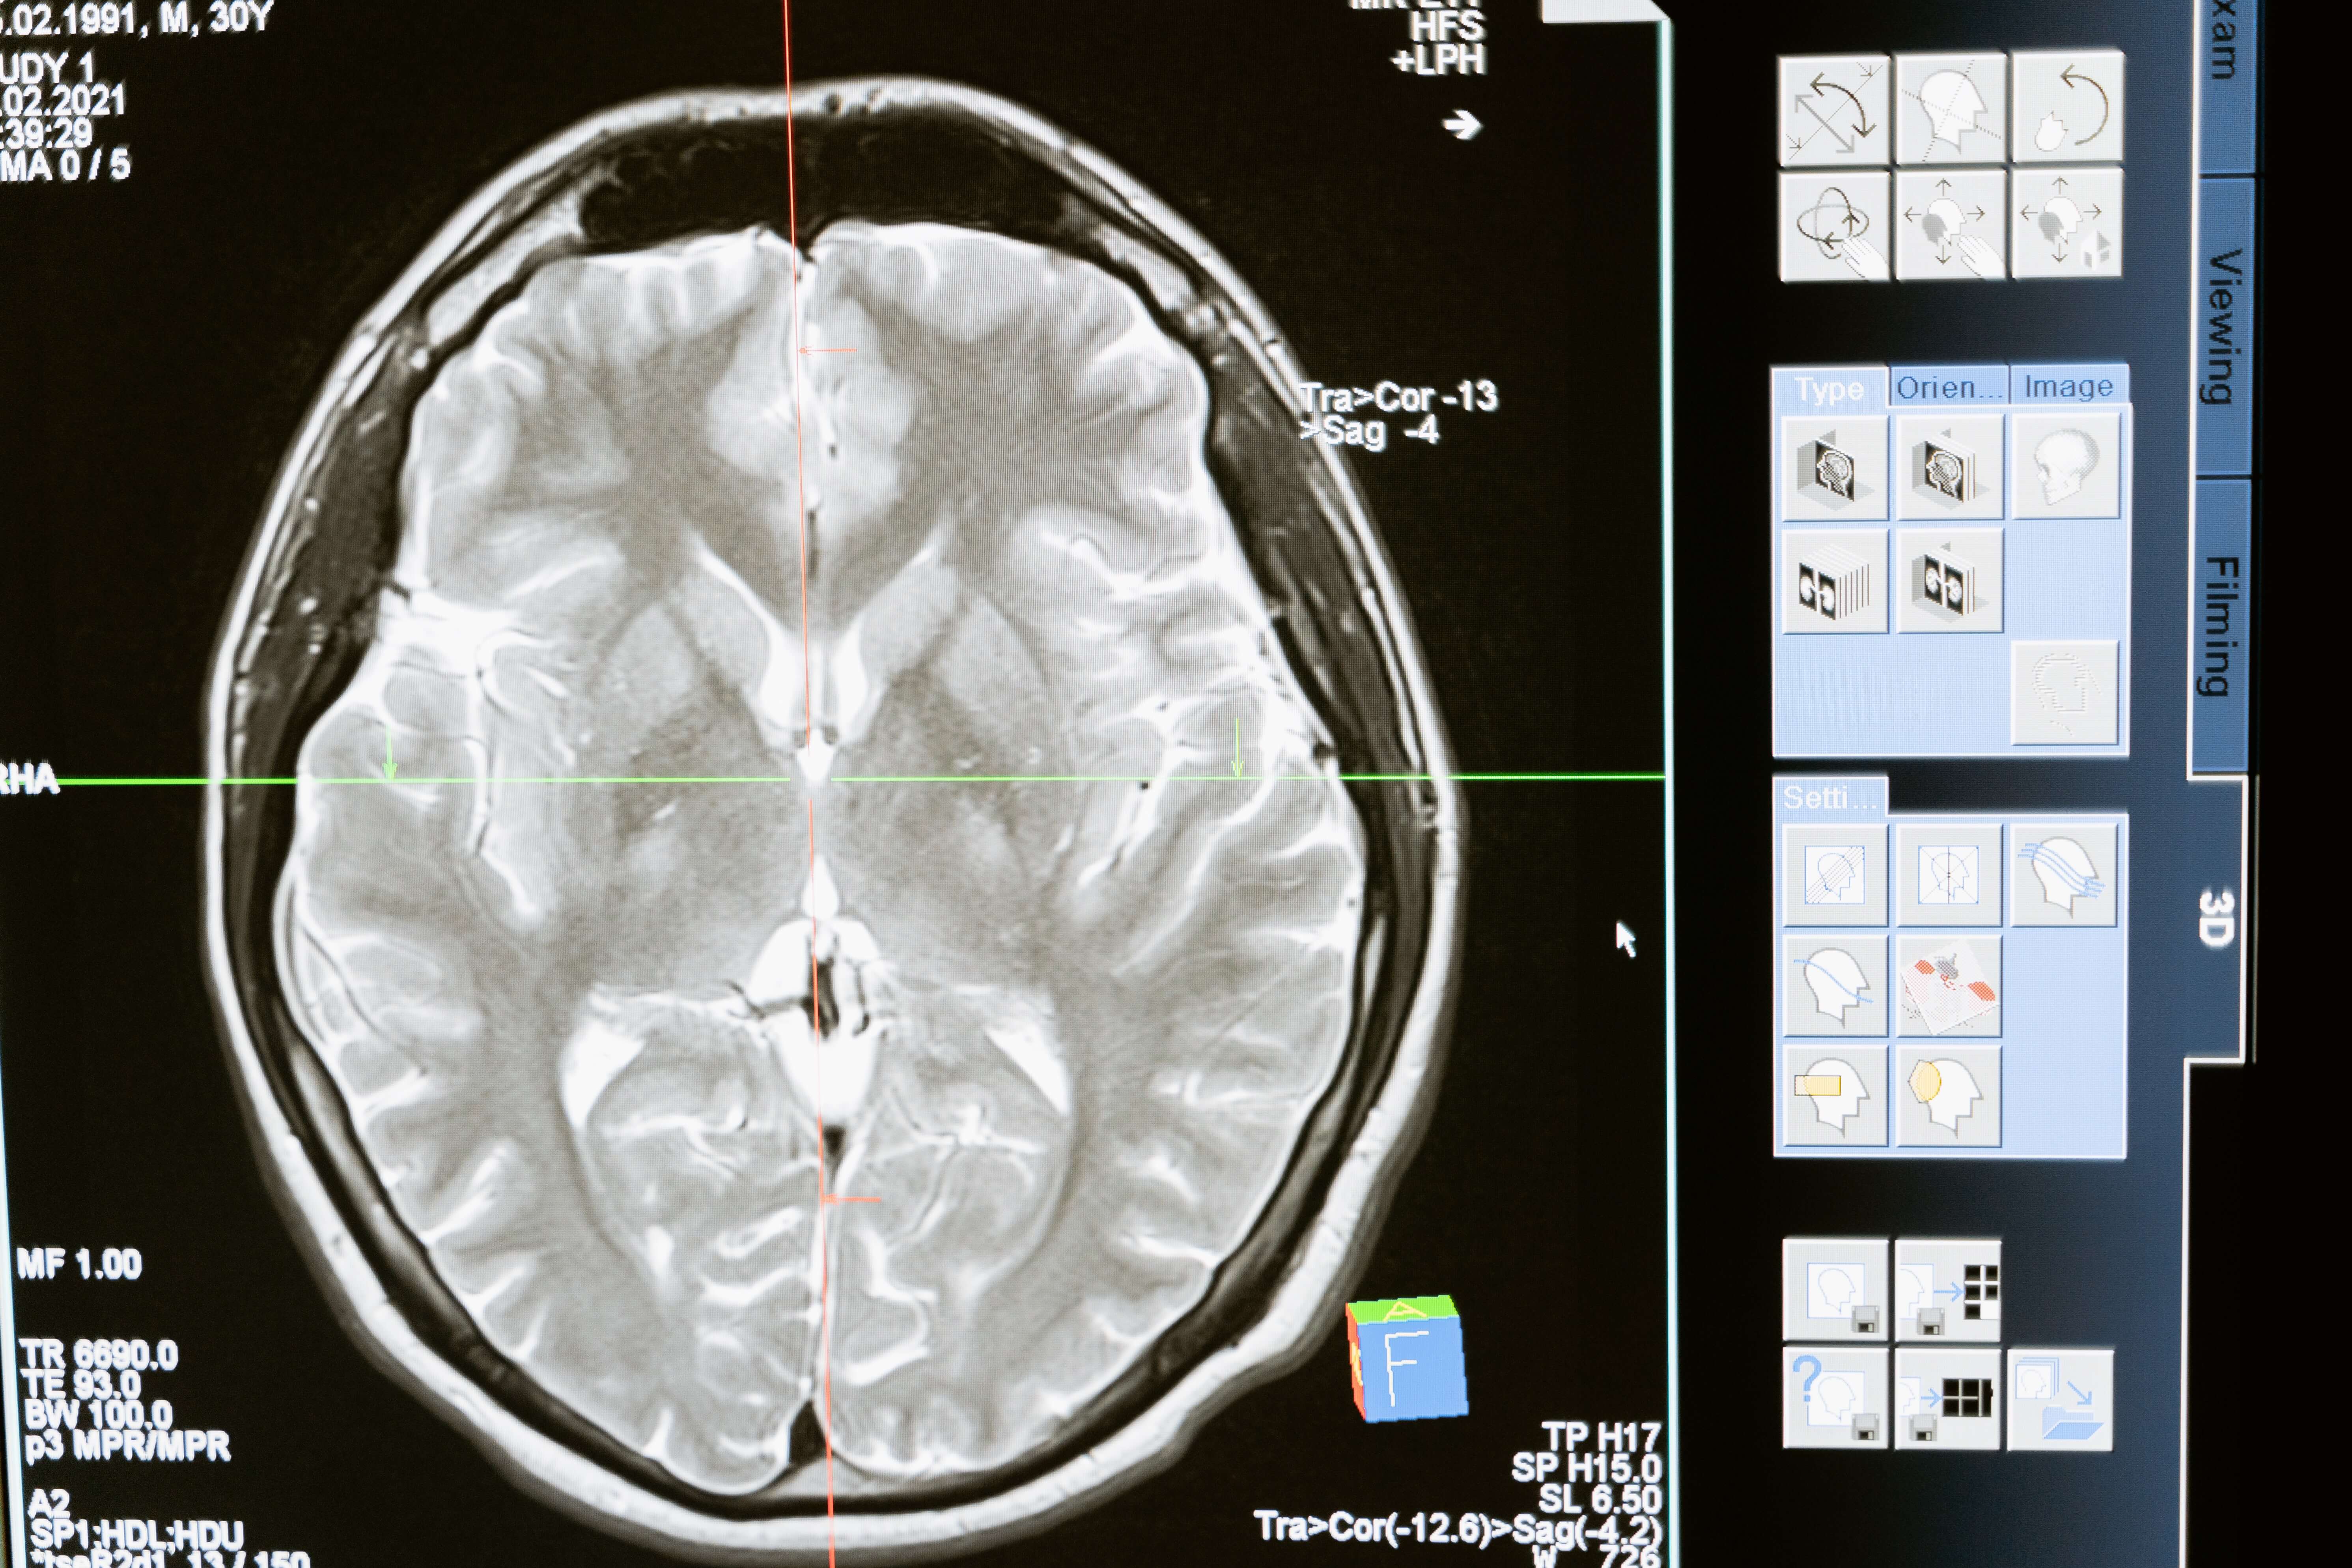

What is Brain Trauma?A TBI occurs when a person’s brain functions are altered because of a sudden jolt to the head or a rapid back and forth movement. In some, the symptoms may be minor and heal quickly with rest and analgesics. In others, it can be catastrophic and lead to death or permanent disability. Brain injuries can occur in a variety of ways:

Injuries are directly related to the type of accident, its impact, and the application of needed therapy. The different varieties of TBI include:

- Concussion: This type can result from an impact to the head or when the brain hits the rough, inner surface of the skull rapidly, such as in a hit and run. It takes several months for a concussion to heal in less severe cases. In other cases, the trauma can result in long-term cognitive changes, headaches, and more.

- Hematoma: A blood clot on the brain’s surface is a hematoma. Blood may collect between the skull and the dura mater, the brain’s protective covering. A small hematoma may resorb, especially in older people. Or, it may press on the brain, requiring surgical intervention.

- Skull fracture: The brain may be damaged if the skull cracks or breaks due to an accident. In addition, a skull fracture can cause seizures and infections by leaking cerebrospinal fluid through the nose or ears.

- Subarachnoid hemorrhage: The resulting bleeding over the surface of the brain is referred to as a subarachnoid hemorrhage. These injuries may be mild, but severe bleeding can cause the fluid to accumulate, which requires surgery.

- Hemorrhage: A bleed inside the brain tissue resembles a stroke. It can take months for people to recover from a brain hemorrhage, depending on its severity.

- Ischemia: A TBI can result in a decrease in blood flow to the brain called ischemia. It can damage the brain even with a slight drop in blood supply due to its sensitivity to change.

- Diffuse axonal injury: In this type of injury, the axons of nerve cells, extensions of the brain, are sheared off by a sudden shift within the skull. Severe damage can result in nerve cells being unable to communicate, causing the messages from the brain to the body to be lost. Not only may the patient suffer severe disabilities but also a higher mortality rate.